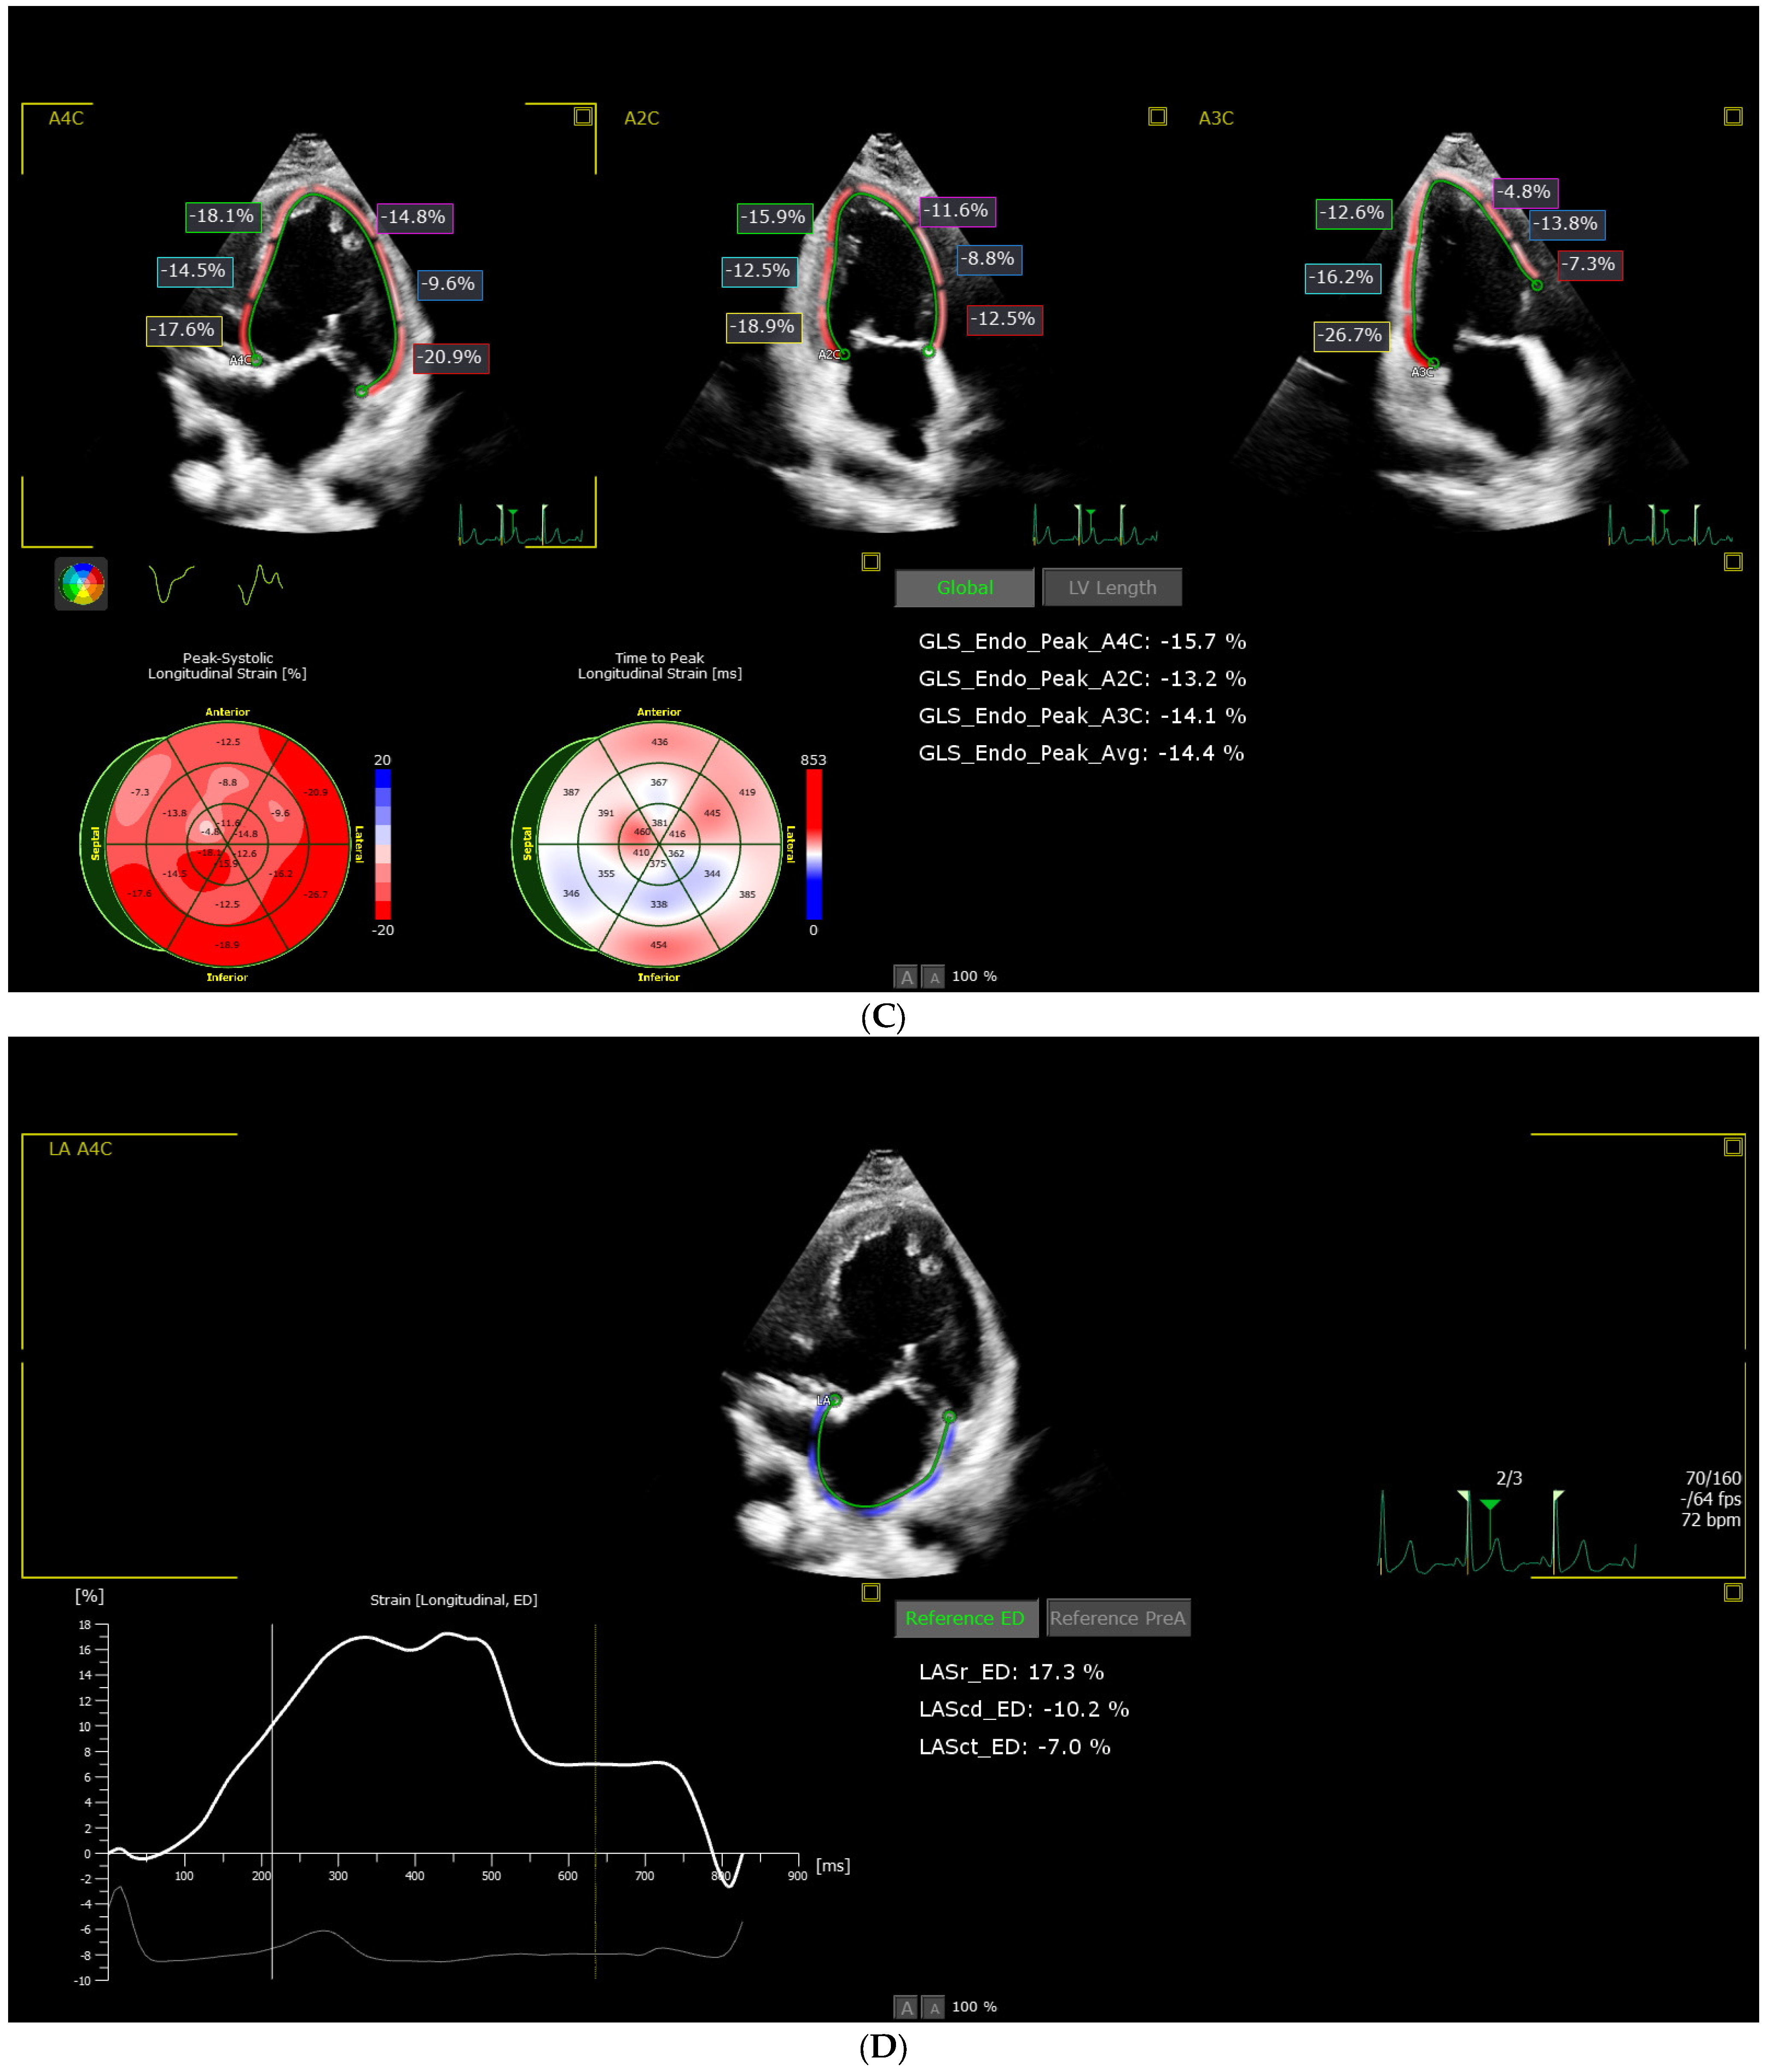

2.2.2. Advanced 3D Echocardiographic Examination

| LV_EF (3D) (%) | 52.50 [46.25, 60.00] | 58.5 [55.00, 62.50] | 0.0025 * (c) | 0.0020 * |